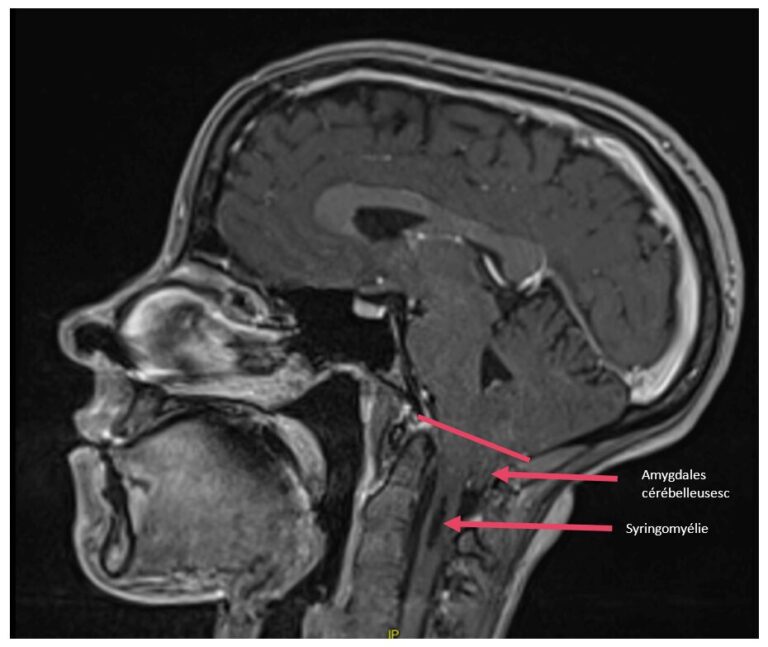

Malformation d’Arnold Chiari avec syringomyélie, post opératoire

Pré et post opératoire, disparition de l’engagement des tonsilles cérébelleuses et diminution de la syringomyélie

La chirurgie correspond donc à un élargissement du trou occipital permettant un repositionnement du cervelet et la levée de la compression du tronc cérébral. Le liquide cérébrospinal peut également reprendre un écoulement classique.